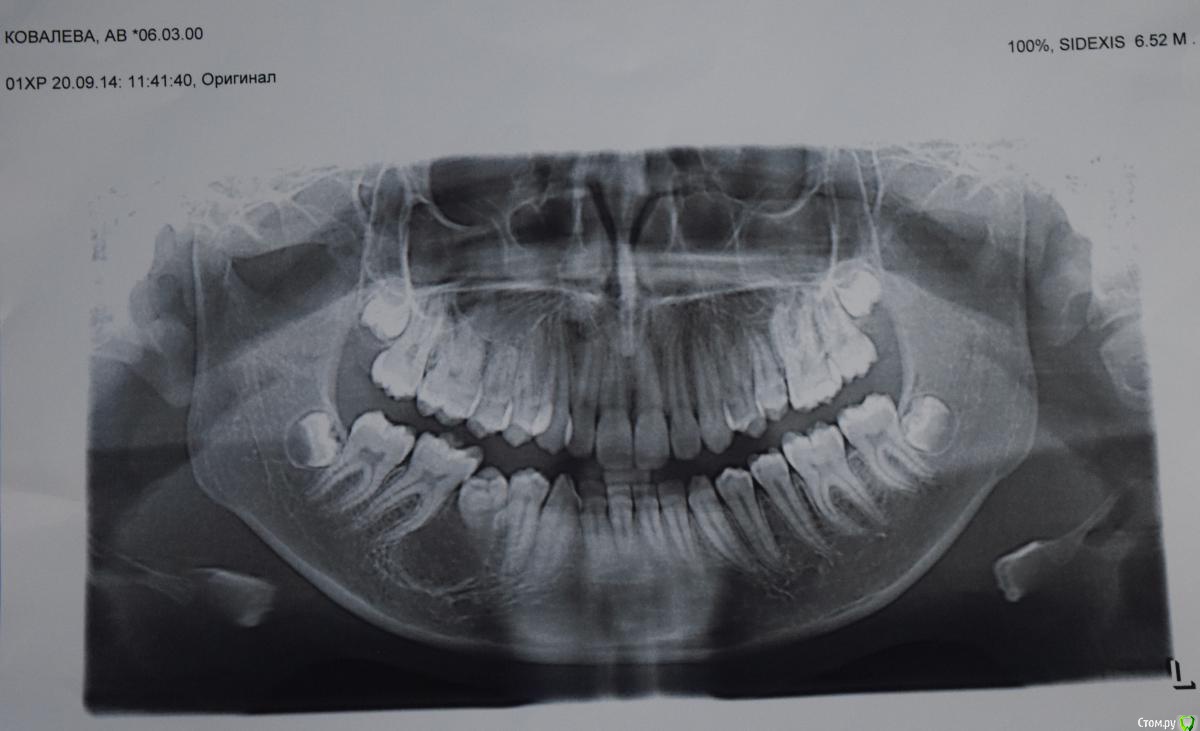

Kovalov Igor Опубликовано 14 июля, 2015 Автор Поделиться Опубликовано 14 июля, 2015 (изменено) Через год ОПТГ снимок Изменено 14 июля, 2015 пользователем Kovalov Igor Ссылка на комментарий